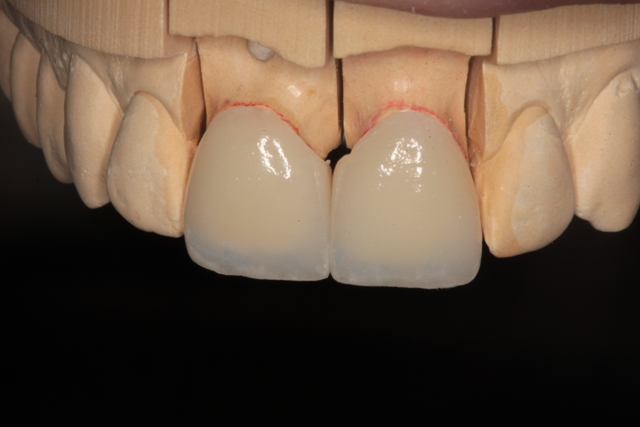

Fig. 7 Fig. 8

Once the case was analyzed and approved for fabrication, a proper ingot was chosen and pressed to full contour. After divesting, the restorations were cleaned and returned to the master cast for inspection of accurate fit. When shaping the restorations, special attention is given to the line angles and surface texture in order to replicate the natural look and feel of the adjacent teeth. The attention was subsequently focused on the photos depicting the natural dentition and their color nuances. Noting the blue color’s intensity and position in the incisal area, the cream colored band framing the edge of the laterals provided me with a mapping for layering purposes. This should also be noted for staining if a monolithic restoration is prescribed. Needless to say the proper preparation, impression accuracy and photo documentation are all necessary to achieve desirable results in any restoration process.

The eMax veneers can be seen on the working model in Figure 7. The intaglio etched surfaces are show on a mirror surface in Figure 8.